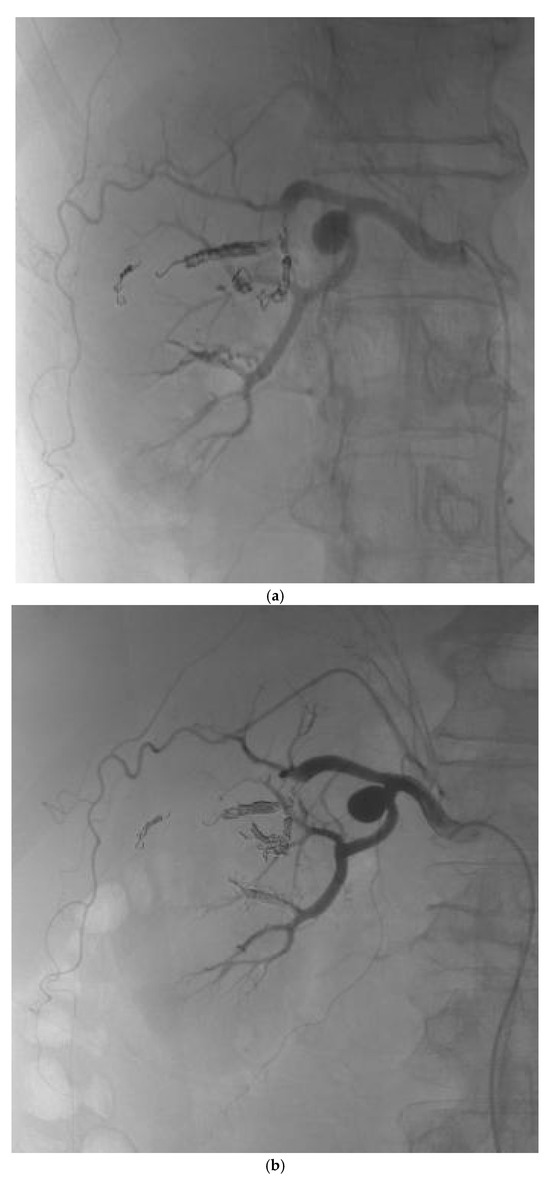

Resolution of Proteinuria After Renal AVM Embolization with Combined ACEi and SGLT2i Therapy: A Case Report

by Ana Mijušković, Jelena Pavlović, Vladimir Cvetić, Borivoje Lukić, Ana Bontić, Selena Gajić, Kristina Filić, Ivana Mrđa, Aleksandar Sič, Nikola Trnić and Marko Baralić

Kidney Dial. 2025, 5(4), 54; https://doi.org/10.3390/kidneydial5040054 - 13 Nov 2025

Background: Renal arteriovenous malformations (rAVMs) are rare vascular anomalies that may lead to hematuria, anemia, or acute kidney injury (AKI). Although endovascular embolization is the treatment of choice, post-procedural complications such as new-onset proteinuria may occur and require long-term management. Case Presentation: A [...] Read more.

Background: Renal arteriovenous malformations (rAVMs) are rare vascular anomalies that may lead to hematuria, anemia, or acute kidney injury (AKI). Although endovascular embolization is the treatment of choice, post-procedural complications such as new-onset proteinuria may occur and require long-term management. Case Presentation: A 56-year-old man with recurrent gross hematuria and elevated serum creatinine (128 μmol/L) was diagnosed with a right rAVM and underwent successful selective embolization. Despite recovery of renal function, follow-up revealed new-onset proteinuria (2.2 g/24 h). Results: Introduction of an angiotensin-converting enzyme inhibitor (ACEi) resulted in partial improvement of proteinuria, while subsequent addition of a sodium–glucose cotransporter-2 inhibitor (SGLT2i) achieved almost complete resolution of proteinuria (0.33 g/24 h) and stable renal function (serum creatinine 93 μmol/L) after 12 months. Conclusions: This case highlights the occurrence of post-embolization proteinuria and illustrates the synergistic renoprotective effect of combined ACEi and SGLT2i therapy in a non-diabetic patient with vascular kidney disease. Full article

Show Figures

Graphical abstract